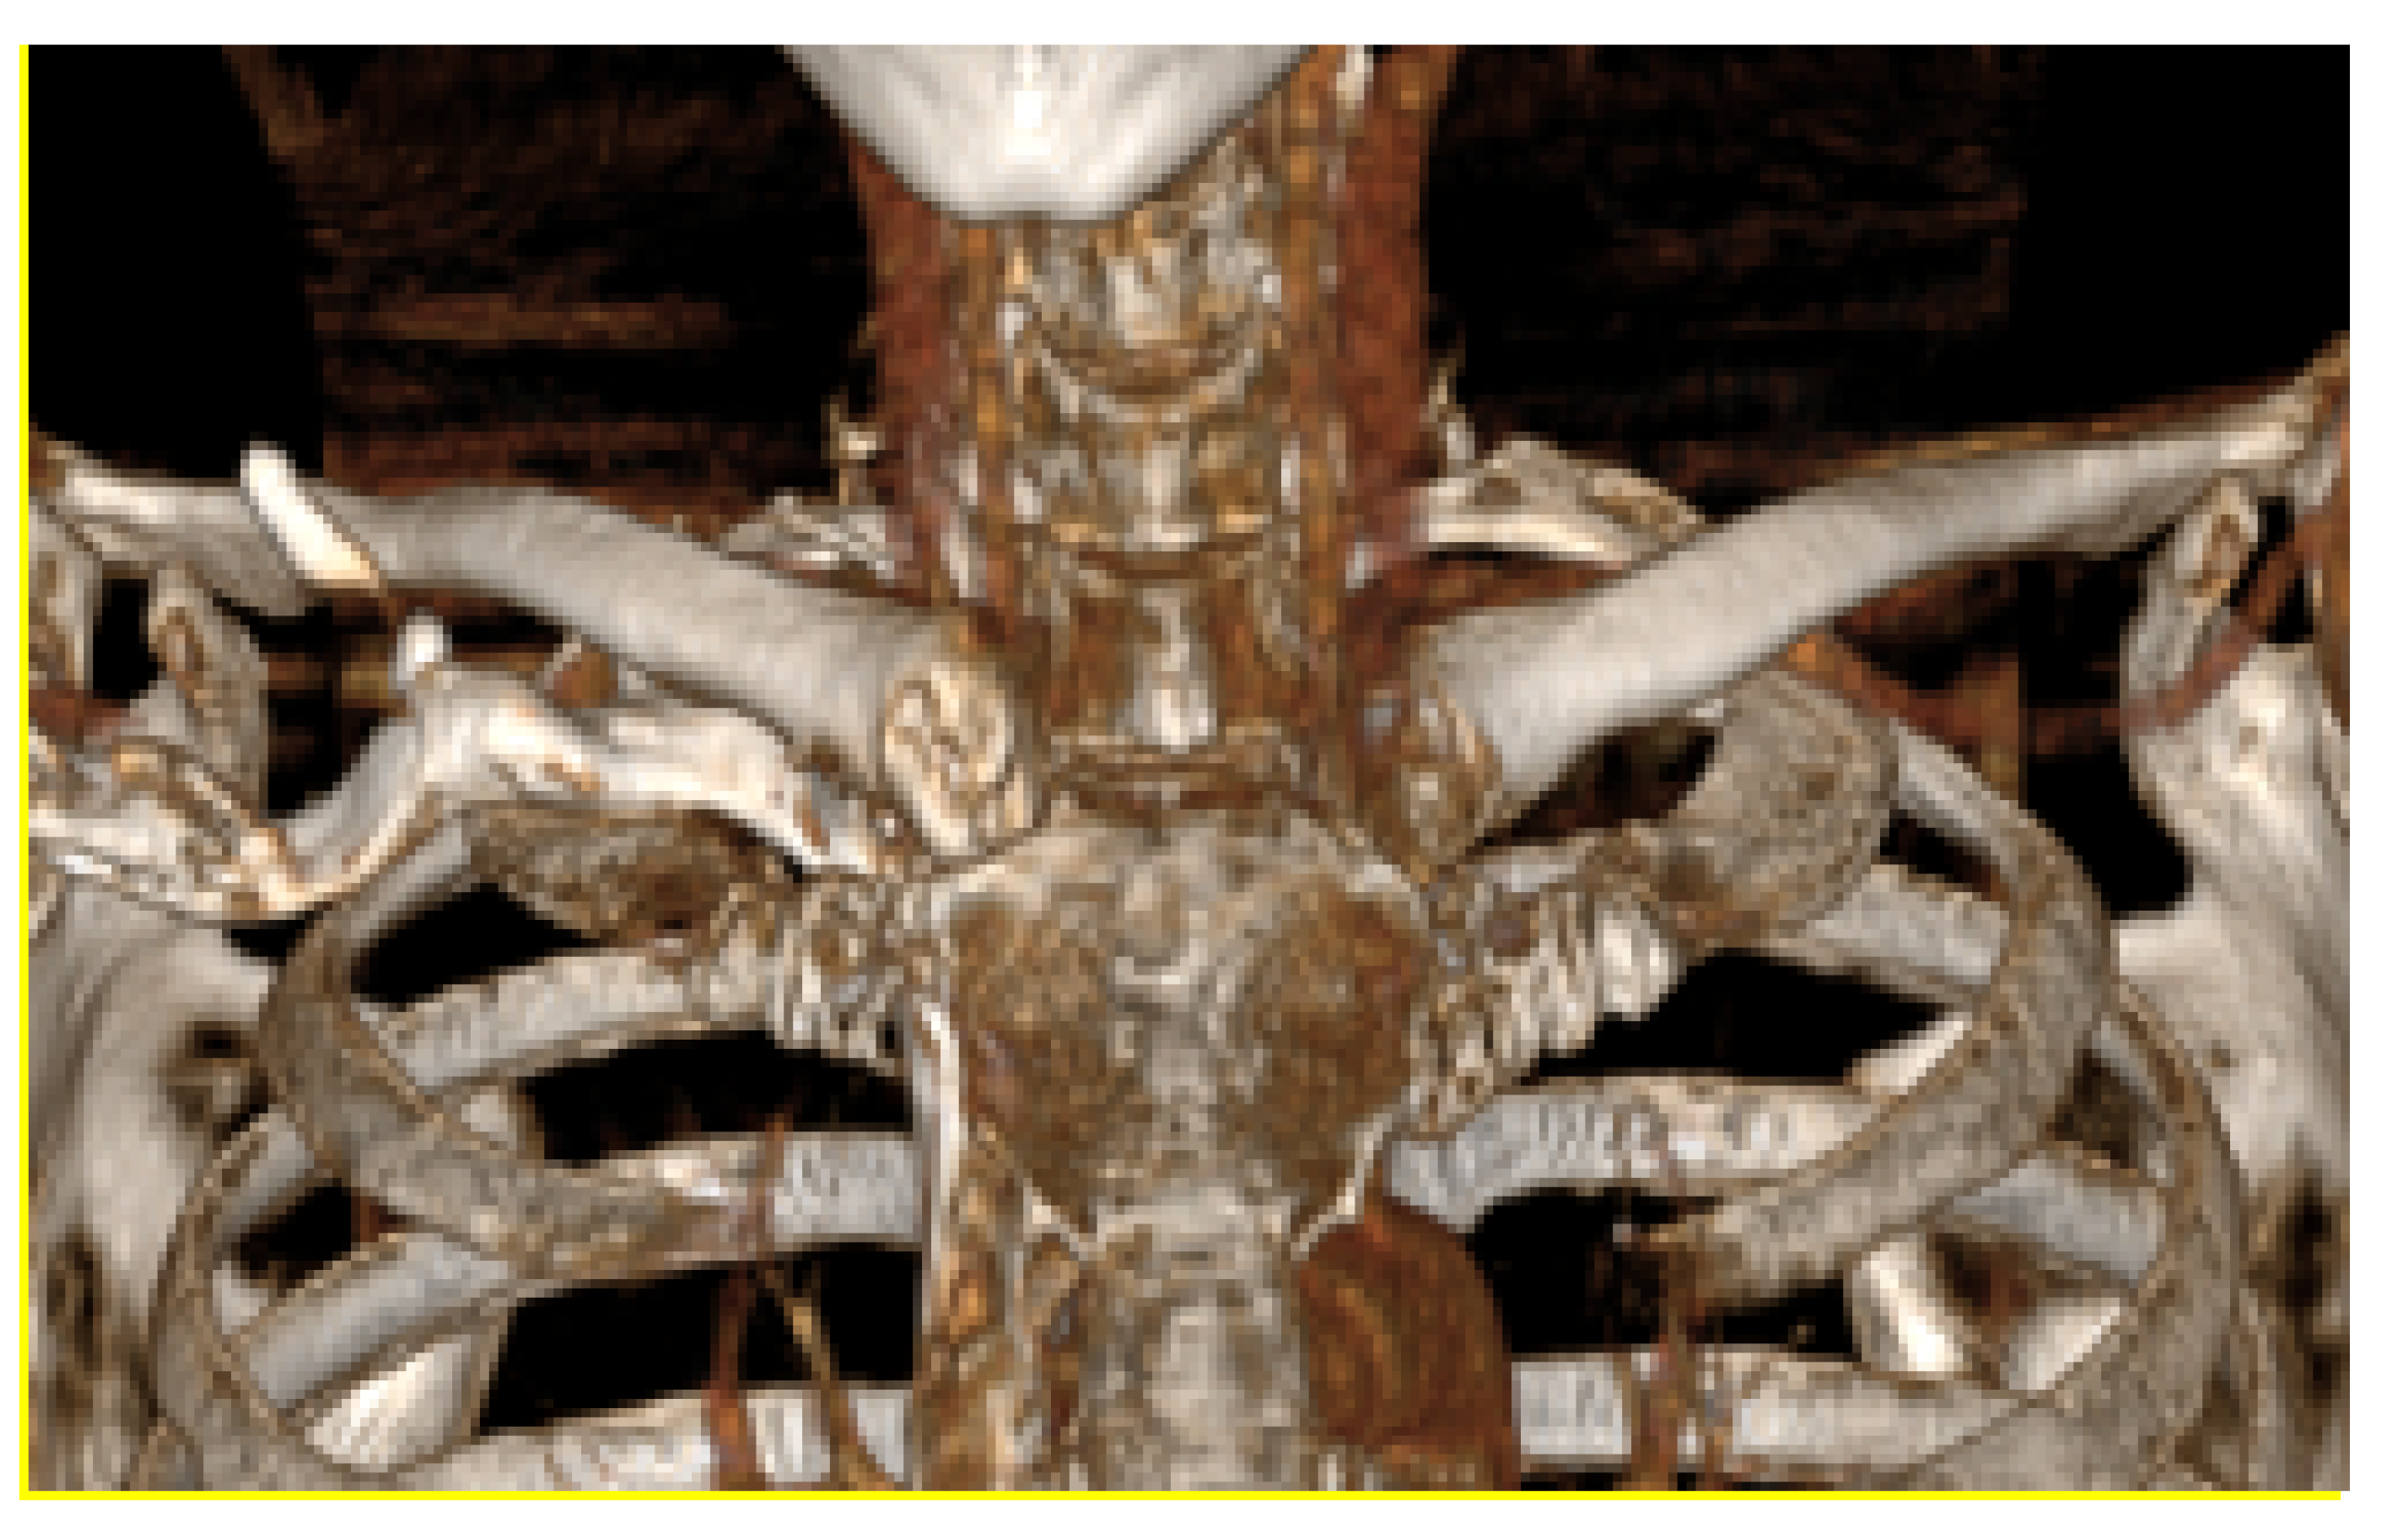

3.4. Case 4: Right Sternoclavicular Joint Tumour

3.4.1. Diagnosis and Analysis